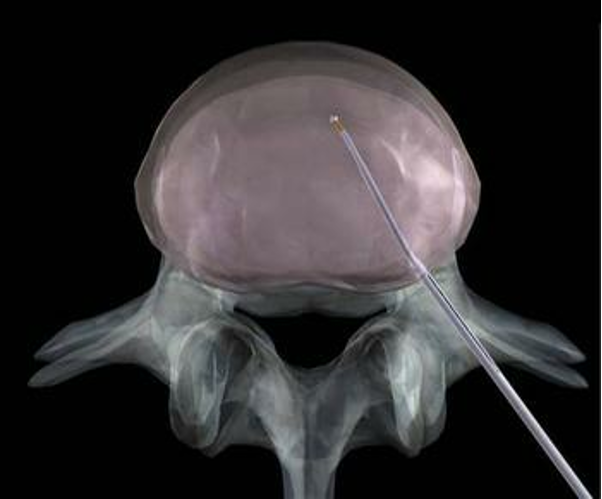

6、经皮激光腰椎间盘减压术(PLDD)利用激光能量使病变的髓核内空洞化,降低椎间盘内的压力,缓解和消除对坐骨神经或脊神经的压迫而达到治疗的目的。

PLDD优缺点在C型臂的透视监测下,把穿刺针刺入颈椎病变的椎间盘中。然后,将光导纤维置入穿刺针里,通过激光的热能将椎间盘髓核汽化,形成了一个空洞,即降低了椎间盘内的压力,改善了神经受压迫的状况。另外,通过激光所产生的生物学热效应辐射到受压迫神经周围,改善了患处的微循环,可以缓解神经症状。PLDD避免了其他盘内减压手术方法的缺点如明显的软组织损伤、广泛的护理、长时间的护理、以及较大的侵入路径。但是其高昂的治疗费用严重的限制了其进一步的应用。PLDD的电极昂贵,并且只能一次性使用,每个电极的成本都在数千元。